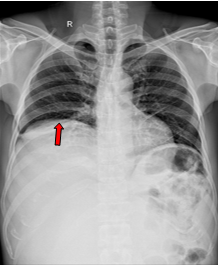

- Xquang ngực: Vòm hoành phải bị đẩy lên cao, dải xẹp phổi mảnh đáy phổi phải.

Hình 1. Hình ảnh chụp XQ ngực thẳng: vòm hoành phải bị đẩy lên cao do u chèn ép (mũi tên đỏ).